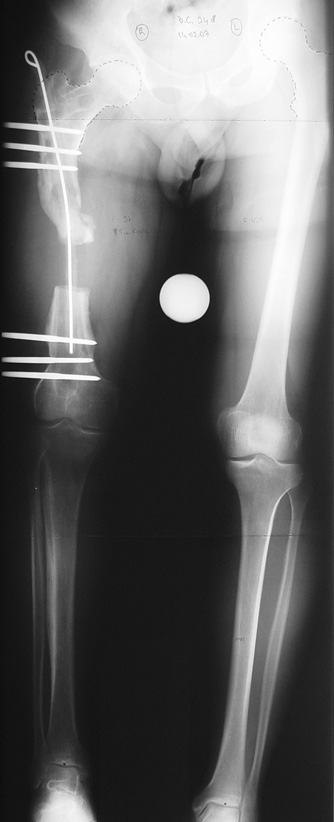

Case 2